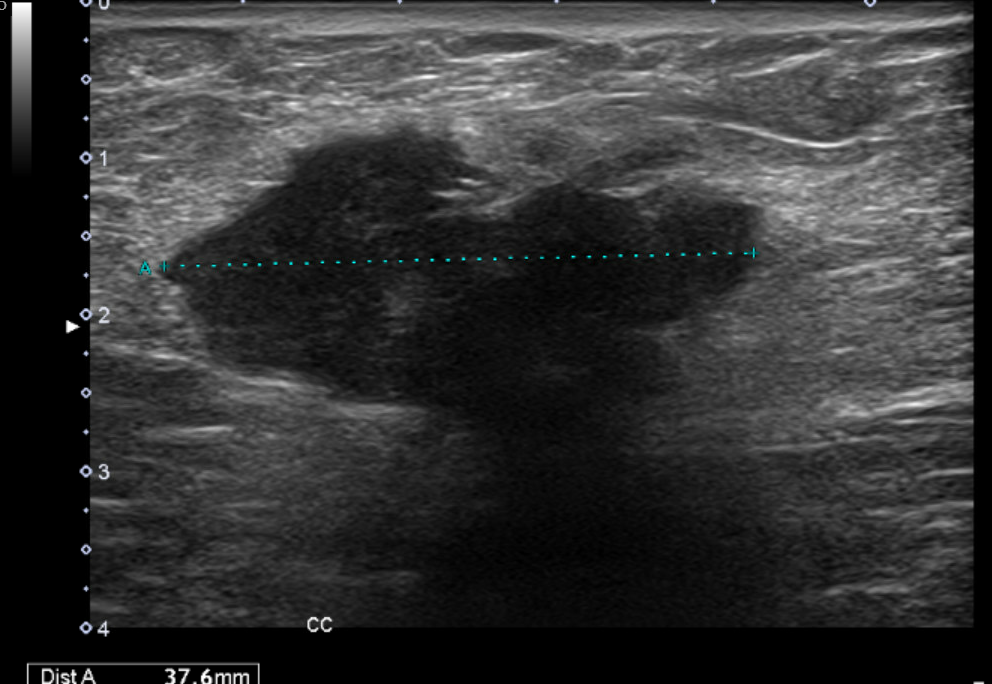

Ecografía clínica partes blandas y abdominal en Centro de Salud: dos nódulos subcutáneos hipoecogénicos, heterogéneos, lobulados y de bordes irregulares (16 x 18 mm), no vascularizados. Abdomen: sin signos patológicos relevantes ni Ascitis ni líquido en Douglas no adenopatías retroperitoneales. Completamos estudio de nódulos sospechosos de malignidad con tomografía abdominal y ecografía de partes blandas reglada.

Ecografía reglada de partes blandas: Nódulos subcutáneos e intrabdominales sospechosos de malignidad. La tomografía abdominal describe múltiples implantes sólidos peritoneales y en pared abdominal, compatibles con metástasis.